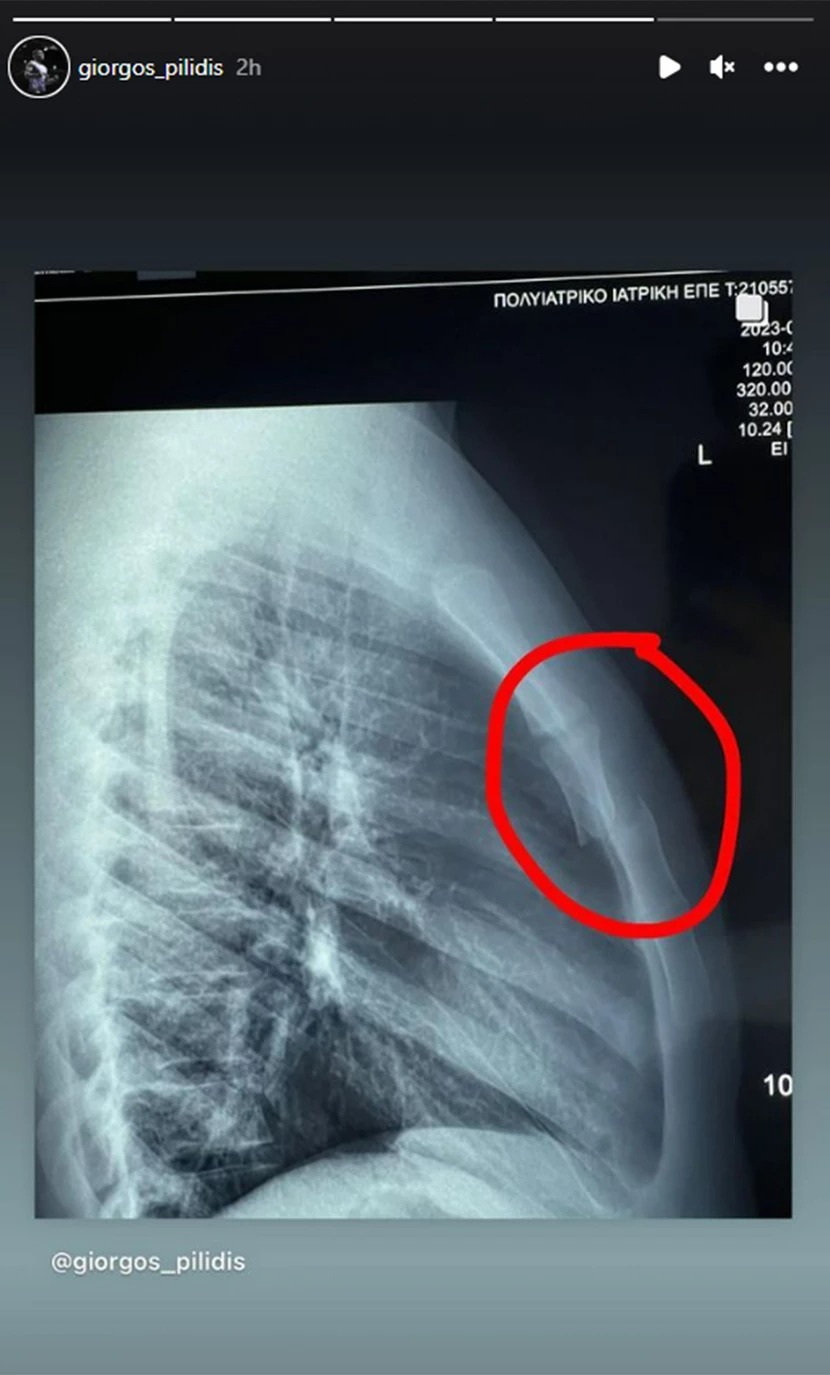

Σοκαριστικό ατύχημα κατά τη διάρκεια ενός αγώνα είχε ο Γιωρίκας Πιλίδης. O αθλητής και πρώην παίκτης του Survivor, αποκάλυψε με μία ανάρτηση στον προσωπικό του λογαριασμό στο Instagram ότι κατά τη διάρκεια του αγώνα έσπασε τον θώρακά του.

«Εάν έχανα τον αγώνα σίγουρα δεν θα μίλαγα… Στο 3 δευτερόλεπτο του αγώνα έσπασα τον θώρακα μου… Γι’ αυτό και δεν μπόρεσα να δείξω όλα για όσα με προετοίμασαν οι προπονητές μου… Δεν είχα ανάσα δεν μπορούσα να χτυπήσω και ποσό μάλλον να παλέψω. Ήταν απλά η χειρότερη εμφάνιση που θα μπορούσα να δείξω… παρόλα αυτά δόξα το θεό για όλα… Ευχαριστώ πολύ τον δάσκαλο μου» έγραψε ο Γιώργος Πιλίδης.